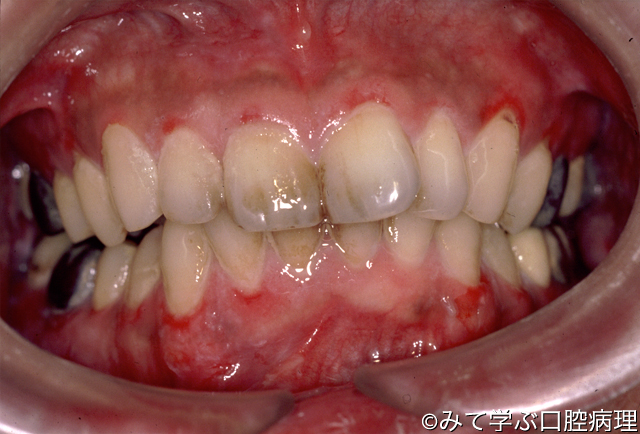

天疱瘡

歯肉の広範囲にびらんがみえる